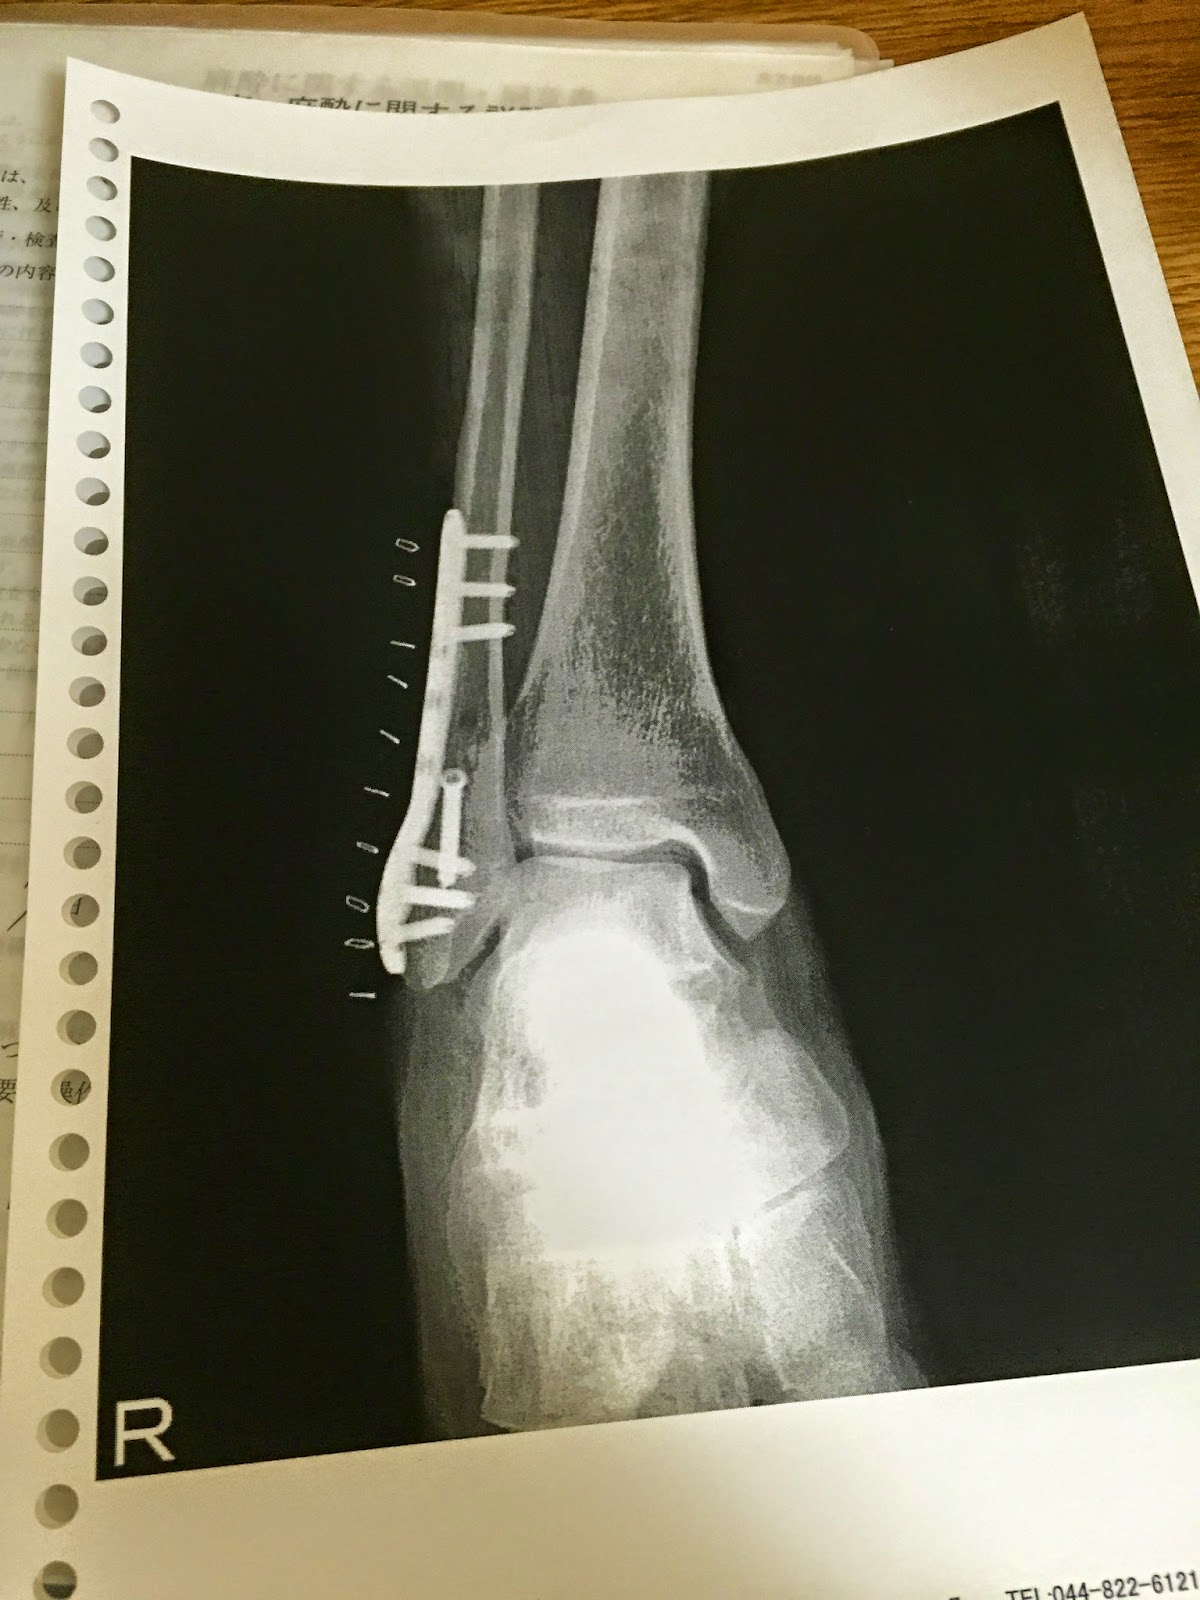

手術が終わりプレートで固定。

CTで撮影した手術前の右足。ぽっきり折れています・・・・。

青く見えているのは、固定しているプレートです。